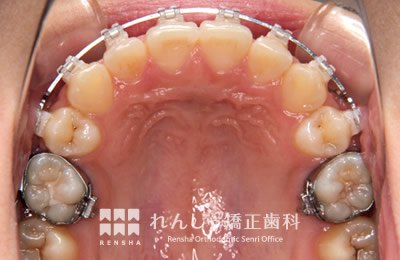

永久歯列はほぼ完成してしますが、歯列を側方だけでなく後方へも拡大し、埋まっていた右上奥歯を引っ張り出しています。

| 主訴 | 埋まったままでてこない歯がある |

|---|---|

| 診断名 | Angle Class II 小臼歯の埋伏と叢生を伴う上顎前突 |

| 初診時年齢 | 13歳5か月 |

| 装置名 | マルチブラケット装置 |

| 抜歯非抜歯 | 非抜歯 |

| 治療期間 | 2年3か月 |

| 費用の目安 | 約82万円+消費税(検査料金、都度の処置費用等も合わせた総額) |

| リスク副作用 | 歯の移動に伴う軽微な歯根吸収、歯槽骨吸収、歯肉退縮(本症例では軽度の歯根吸収を認めた)、矯正器具装着中のカリエスリスク増大(本症例ではカリエス発生無し) |